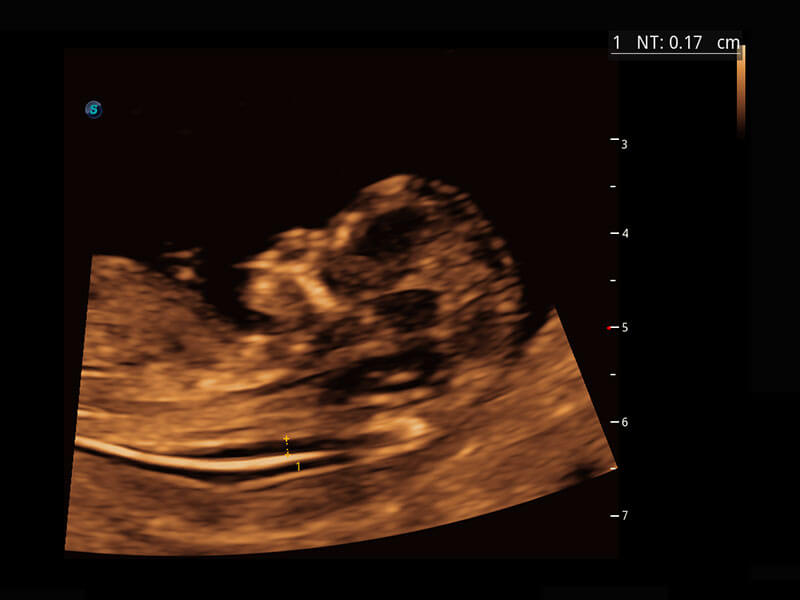

早孕筛查

P60在胎儿早孕期超声筛查中为您带来优异的图像质量。

• 早孕-胎心

• 高分辨率容积成像-早孕胎儿

• 胎儿体循环

• 光影成像-孕囊